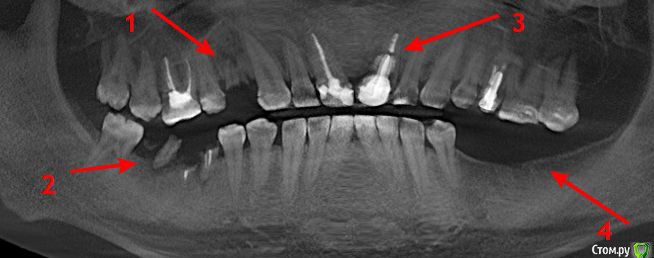

alezx Опубликовано 20 ноября, 2015 Поделиться Опубликовано 20 ноября, 2015 Всем доброго дня. Достаточно давно мне удалили 5 зубов. 9 ноября мне удалили ещё 4 зуба и поставили 8 имплантатов (альфа-био). Удаление и имплантирование прошло одномоментно. К сожалению, я ещё не делал снимок или КТ после имплантации, поэтому схематично могу показать что и где менялось на старых снимках + приложу фото там, где имплантаты видны.Комментарии к снимку:1. Удален зуб, установлен имплантат2. Удалены 2 зуба, установлены 3 имплантат с формирователями3. Удален зуб, установлен имптантат4. Установлены 3 имплантата без формирователя Все обычные последствия прошли достаточно быстро. Отек сошел к концу недели (через 5-6 дней). Болей как таковых не было, кроме первых дней и все казалось бы шло, как по маслу. Но примерно с 15 числа появилась глубокая (не знаю как верно это назвать, то есть она была не сильной и как будто где-то в глубине кости) боль с правой стороны нижней челюсти. Решив, что это просто часть последствий после тяжелой операции принял кетанов и постарался не обращать внимание. На следующий день все повторилось, к вечеру боль вернулась. И так начало повторяться каждый день.Вчера, 19 числа, я снимал швы (у другого врача) и решил проконсультироваться по поводу боли. Мне озвучили, что это вполне нормально и должно скоро пройти.Вечером кетанов решил, что хватит с меня и действовать перестал. Боль уже добралась звоном до уха. Ночь прошла интересно. В 5 утра я выпил нимесил и тогда смог уснуть. В это время боль уже отдавала в крайних нижних зубах при надавливании на них + немного побаливало с левой стороны челюсти (там уже все заросло десной и до этого времени не беспокоило). Разумеется судьба привела меня сюда и судя по прочитанному из других тем, боль на 10 день после операции - это совсем не нормально (успокойте меня, если ошибаюсь).Мысли тревожат вариантами "не прижились имплантаты" или "задет нерв", хотя второе сомнительно, ведь у меня не было онемения.. Хотелось бы услышать ваши мысли по поводу происходящего со мной. Так же уточню:1. Снимок сделаю, вопрос только в его срочности (бежать прямо сейчас с работы или можно подождать начала следующей недели?)2. К сожалению, наблюдаться дальше у того же хирурга, что делал операцию я не могу. Планировал протезироваться в одной из клиник города, но ещё не выбрал в какой. Вариант обращаться даже за переделкой сделаного в то же учреждение - крайний для меня.3. О состоянии 8-рки в курсе, стоматологию планировал после этой операции. (Опять же, на форуме прочел, что пишут об обратном (лечение-удаление-имплантация), но на момент косультации со стоматлогом было озвучено "Удаляй все, потом приходи". Только вот не знаю, приходить ли к нему...) Ссылка на комментарий

Vitasem Опубликовано 28 ноября, 2015 Поделиться Опубликовано 28 ноября, 2015 Вполне возможно пульпит в 8ке - на первом снимке видна под эмалью полость, хотя на двух других не очень видна.Да и по смптомам(боли ночью) больше смахивает на пульпитВизуальный осмотр, препарирование 8го для исключения его как источника боли.Может еще и формирователь в 1м импланте в области 46 поджимать кость.Пока по теперешним рекомендациям пополощите рот р-ром хлоргексидина 0,5%.Почистили зубы и набрали 1 стол ложку и 2-3 минуты пополоскали.ПС. Через месяц - два - нежно будет проверить жизнеспособность 13, если нерв погиб - эндодонтия. (верхушка импланта рядом с верхушкой 13. Ссылка на комментарий